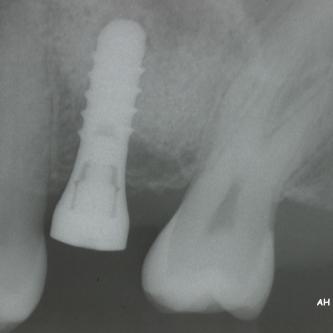

Exemple 14: Radiographie post chirurgicale.

Exemple 14: 6 mois plus tard, l'implant est introduit dans cette greffe sans toucher le sinus.